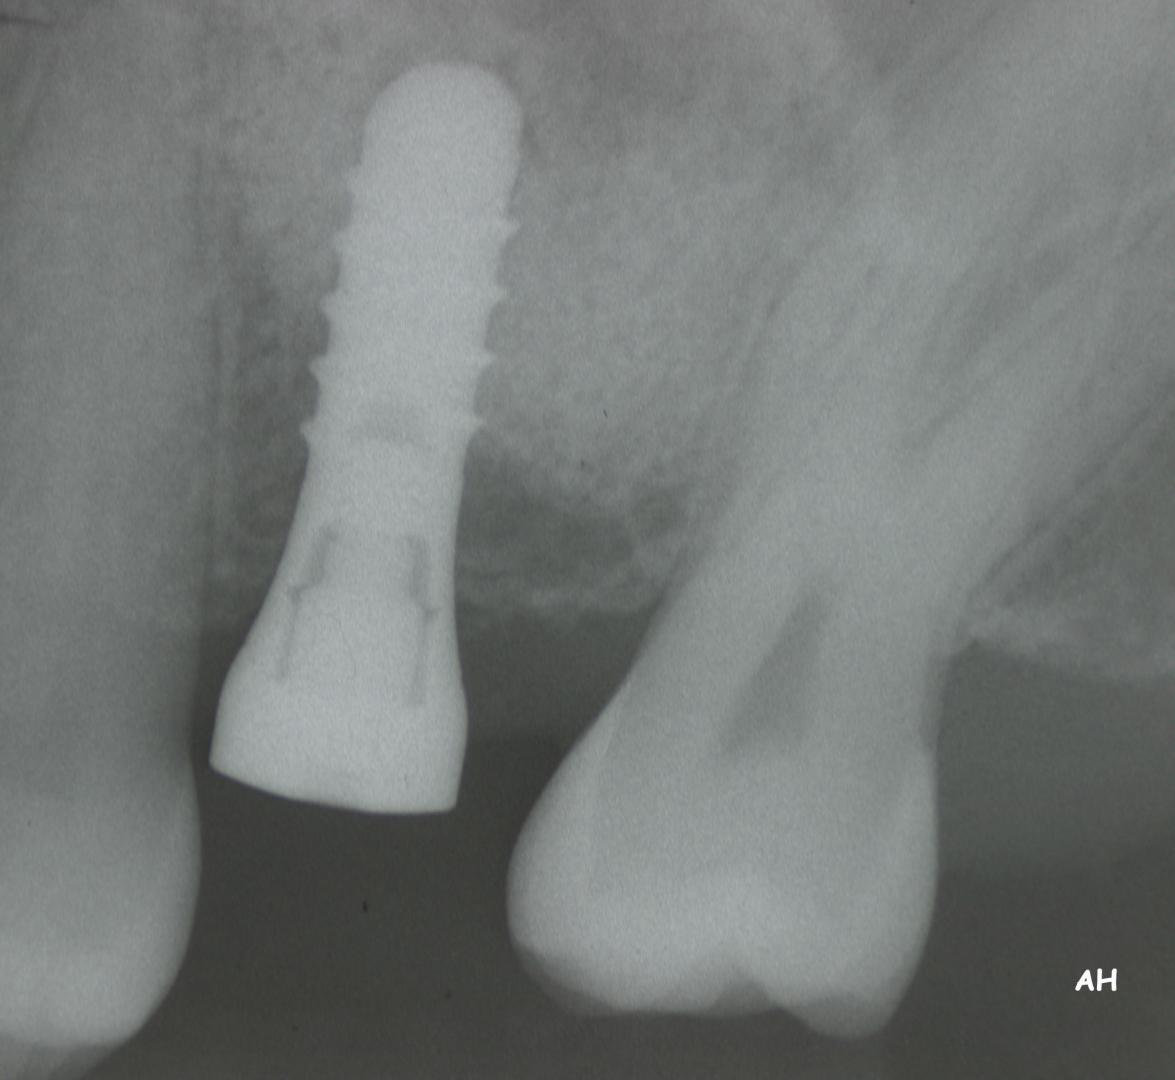

Exemple 2: Un implant remplaçant la racine d'une molaire inférieure gauche.

Exemple 2: La couronne en céramique scellée sur cet implant.